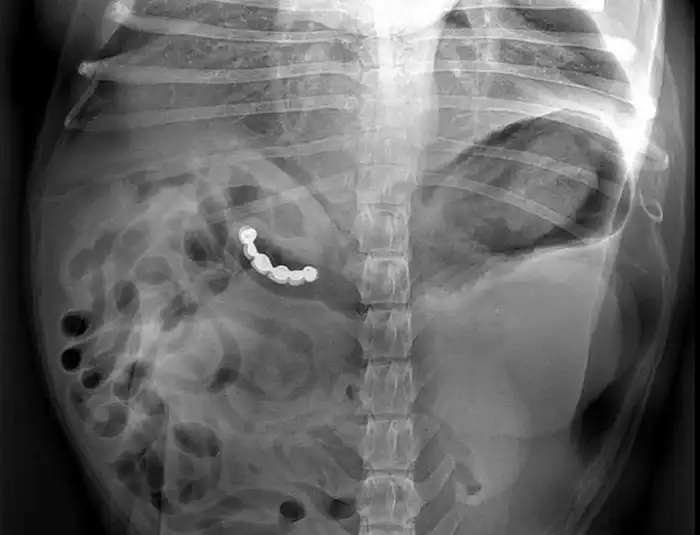

52-летняя Маргарет Даалман просто захотела поесть серебра, поэтому навернула 78 ложек и вилок.